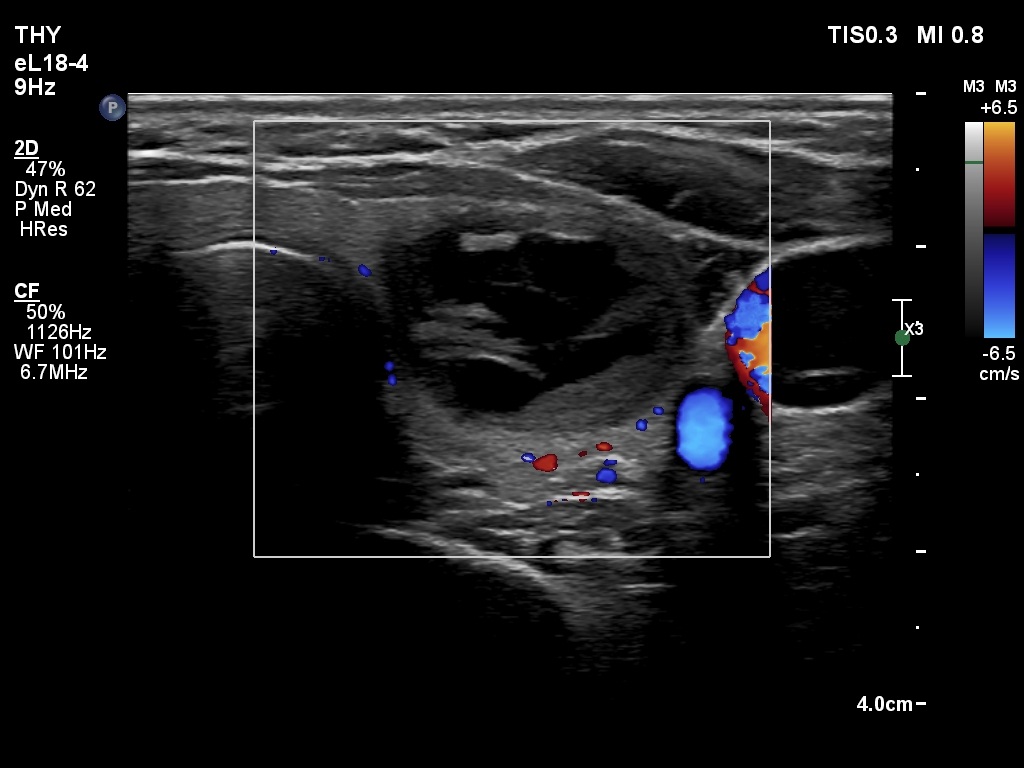

First examination (first and second rows of images)

Clinical presentation: A 39-yr old woman was referred for evaluation of a thyroid cyst which has refilled twice in the past. On the last aspiration, 2 years ago the maximal diameter of the nodule was 24 mm.

Palpation: no abnormality.

Laboratory test: 2.71 mIU/L.

Ultrasonography. The thyroid was echonormal. There was a central-type cystic nodule in the left lobe. The solid portion was echonormal-minimally hypoechoic. The lesion showed back wall cystic figures.Cytology was performed from the lesion in the left lobe and resulted in benign, cystic-colloid goiter.

Suggestion. Ultrasound in two years, in the event of complaints at once. If the cyst would recur ethanol sclerotherapy is advised.